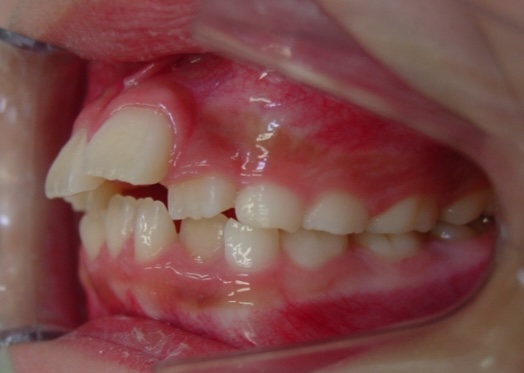

矯正前